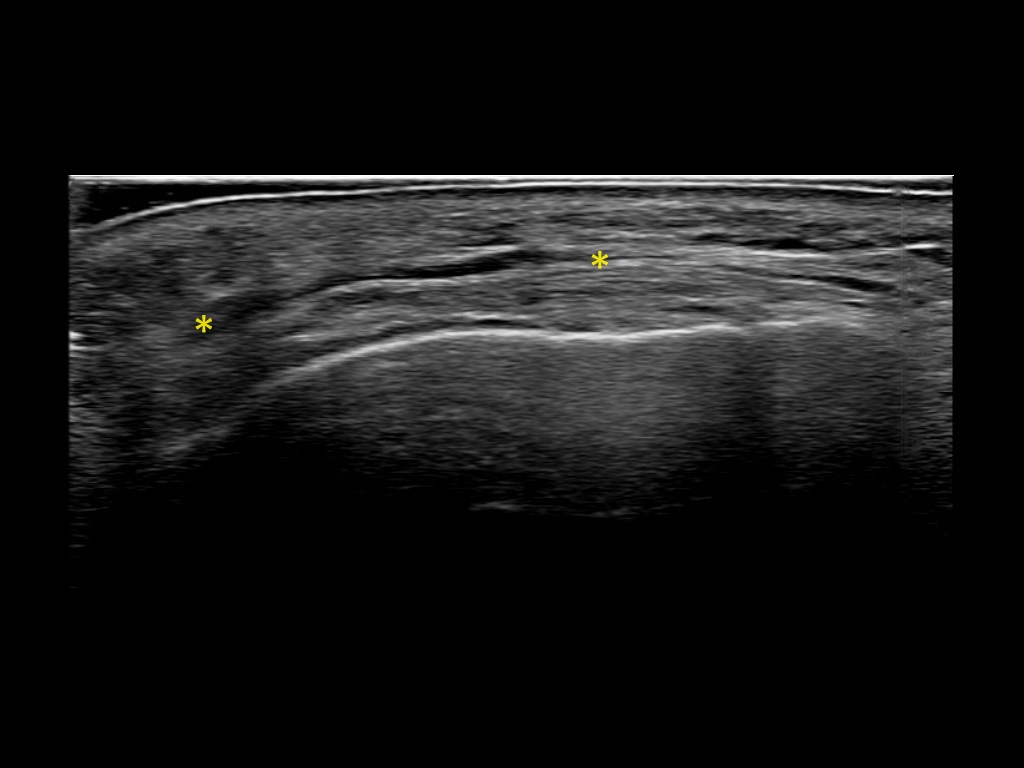

Filler deposits may end up unintentionally in the SMAS or fascial layers of the skin. Very often this will not lead to adverse events, however, adverse events ( nodules, migration / redistribution impaired muscle movement and smiling and malar edema) are are often related to filler ending up in the SMAS or fascia.

Study the first image to recognize the different layers. If you are sure about the layers, swipe to the second image to view the answer (if applicable).